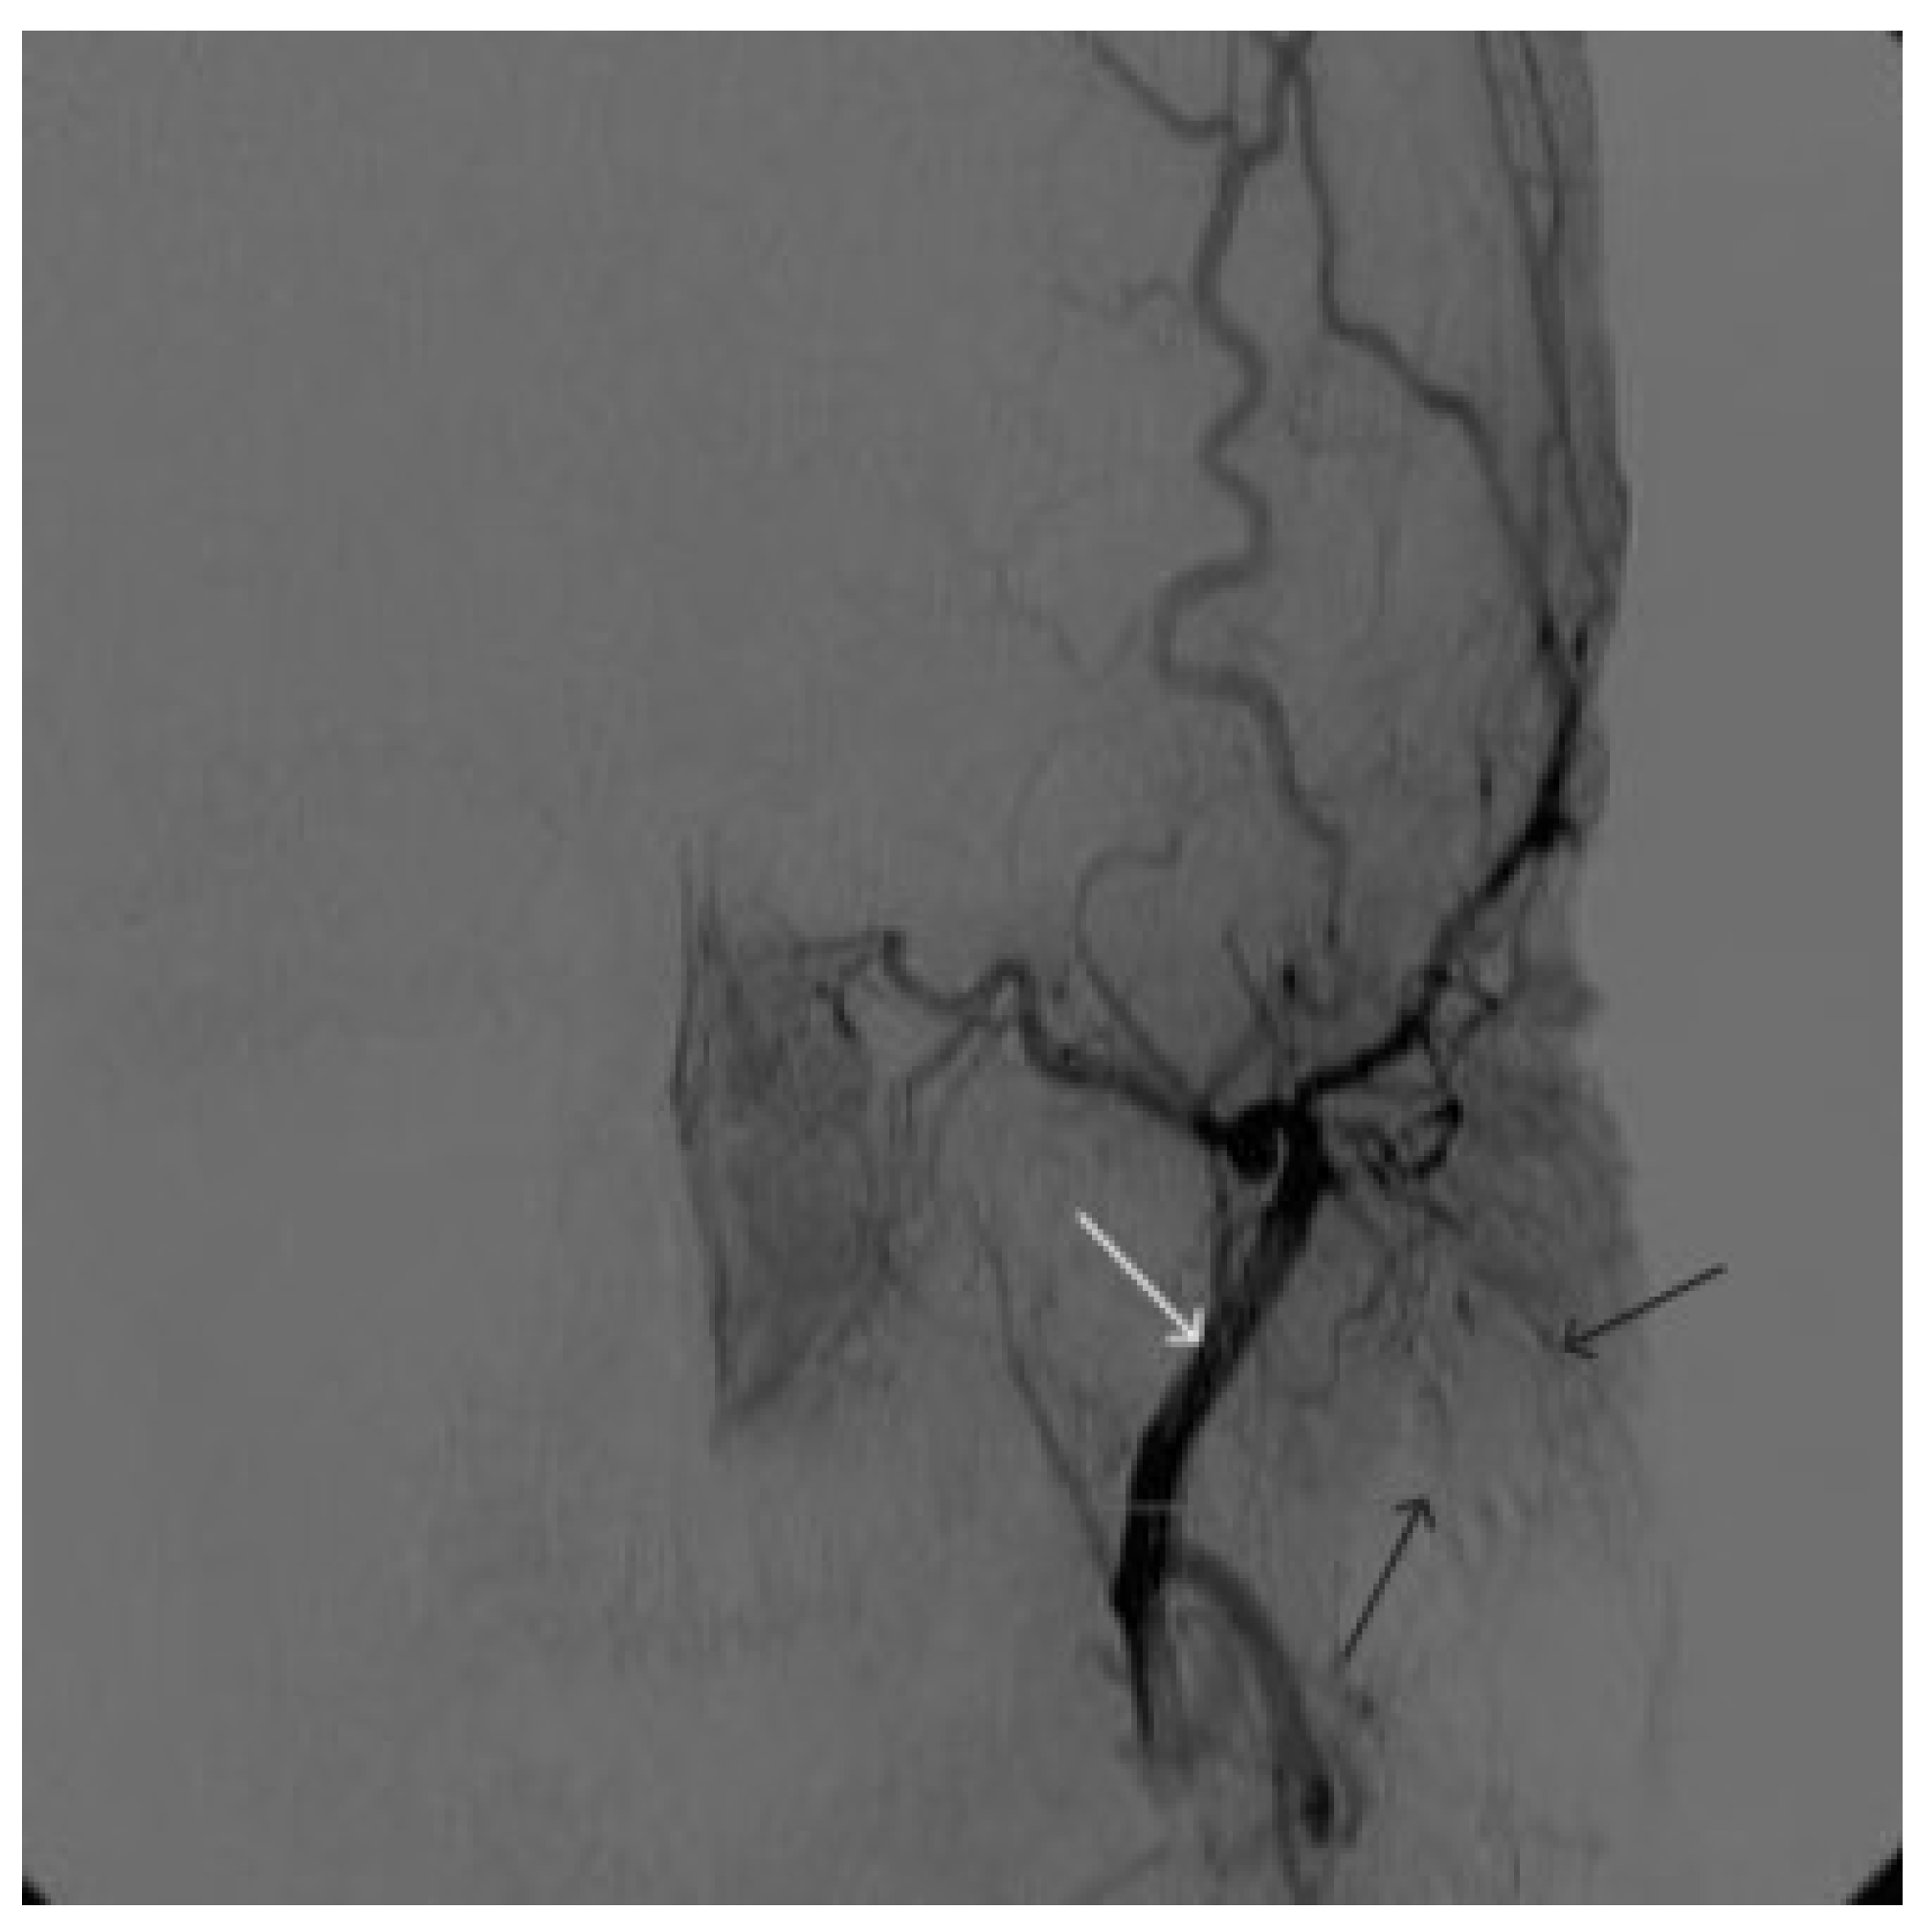

A 58-year-old male patient was admitted to the clinic complaining of a palpable formation in the left submandibular region. When angiography was performed, the filling of the vascular network of the tumor of the left submandibular region from the branches of the left occipital artery, as well as the muscular branches of the left vertebral artery, was noted (Figure 11). The patient underwent intravascular embolization of the paraganglioma with 7.5 mL of non-adhesive composition ONYX18 (Figure 12 and Figure 13). The vascular network supplying the paraganglioma was partially switched off (Figure 14). There were no complications. The mRs score at discharge was 1.

Figure 11. Digital subtraction angiography from the left common carotid artery: (a) direct projection, (b) lateral projection (white arrows indicate the left internal carotid artery, long black arrows indicate the external carotid artery, short black arrows indicate the boundaries of the paraganglioma).

Figure 12. Distribution of ONYX18 along the vascular network of the paraganglioma: (a) direct projection, (b) lateral projection (white arrows indicate filling of the vascular network of the paraganglioma, black arrows indicate an inflated balloon in the left internal carotid artery).

Figure 13. X-ray in single shot mode. (ac) Demonstration of gradual spreading of ONYX18 (NAGLEMs cast) through the vascular network of the paraganglioma direct projections (black arrows indicate filling of the vascular network of the paraganglioma, white arrows indicate an inflated balloon in the left internal carotid artery).